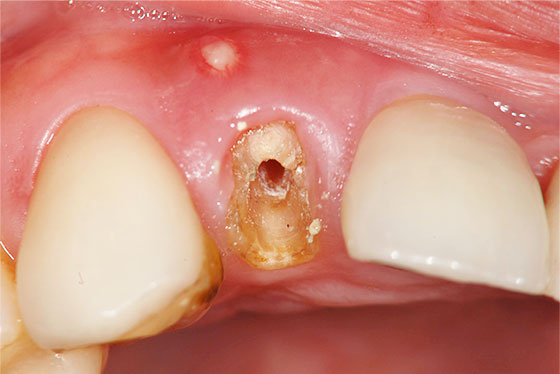

歯の上部が割れた場合と、歯の根が割れた場合とでは、治療法や治療の難易度が異なります。「歯の上部」が割れた場合は、基本的に抜歯せずに治療が可能です。しかし、「歯の根」が割れた場合、多くのケースは抜歯の選択となります。

しかし、「歯の根」が割れた場合でも、一度、その歯を意図的に抜歯し、割れた部分を処置して再度元に戻す「意図的再植術」を行うことで最終的には抜歯せずに治療ができることもあります。

以下、他院で「抜歯」と言われた歯を残したケースになります。

他院で「歯の根が割れてるので、抜歯になります」と言われた場合でも、実際は割れておらず、通常の根管治療で対応ができる場合があります。